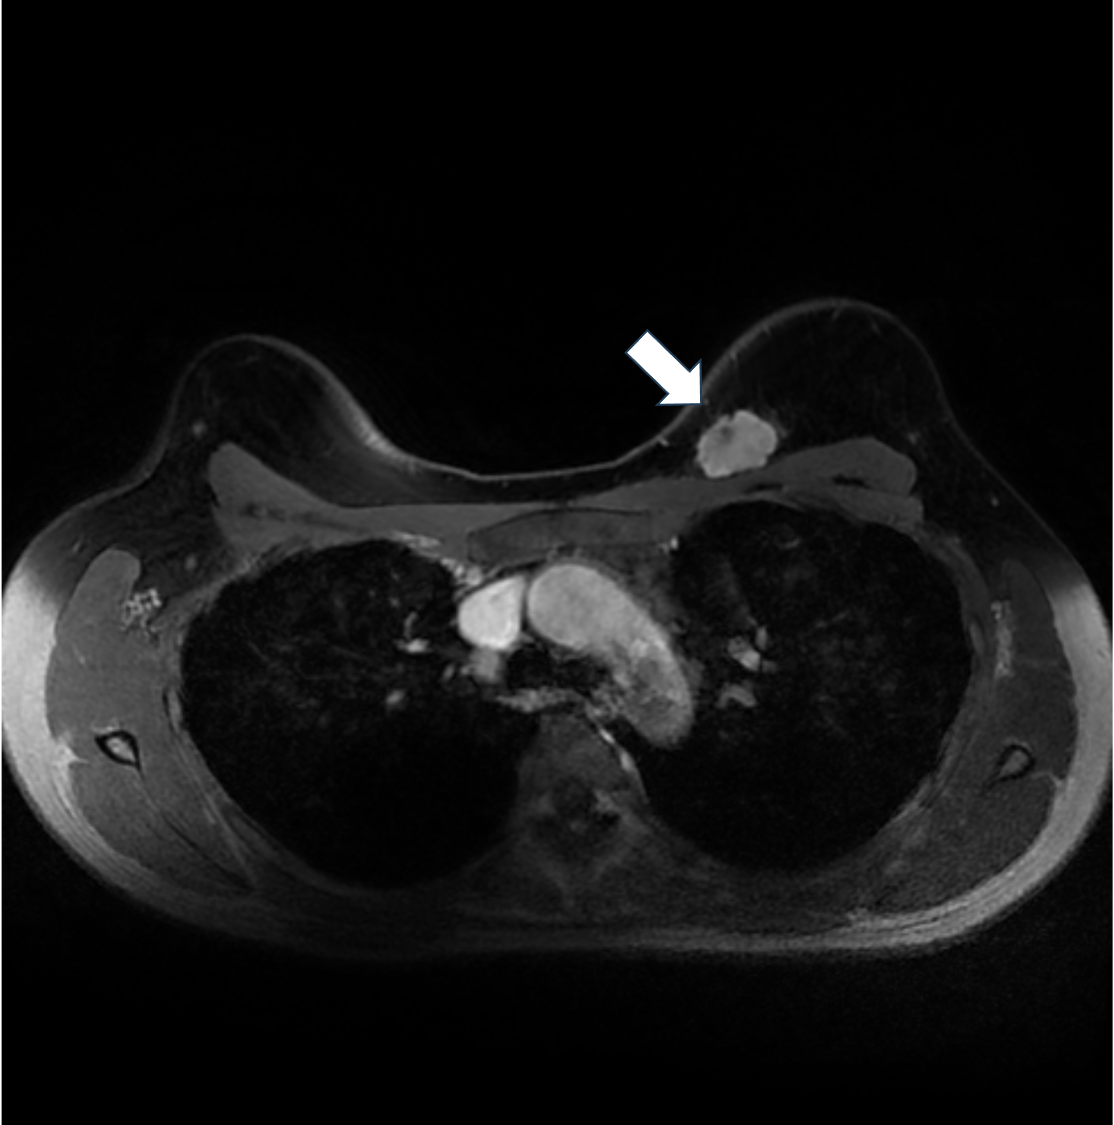

5. ダイナミックMRI 早期相

ダイナミックMRIでは不整形、境界不明瞭な腫瘤でfast-plateauパターンの不均一な造影効果を示す。